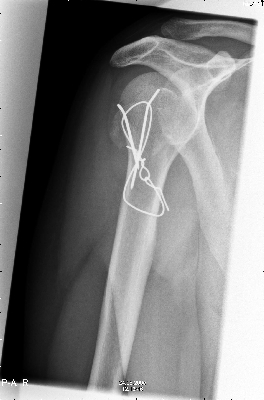

Maar op 9 augustus bleek dan niet zo te zijn en moest er de volgende dag geopereerd worden. |

| na de operatie was alles weer vast gezet. |